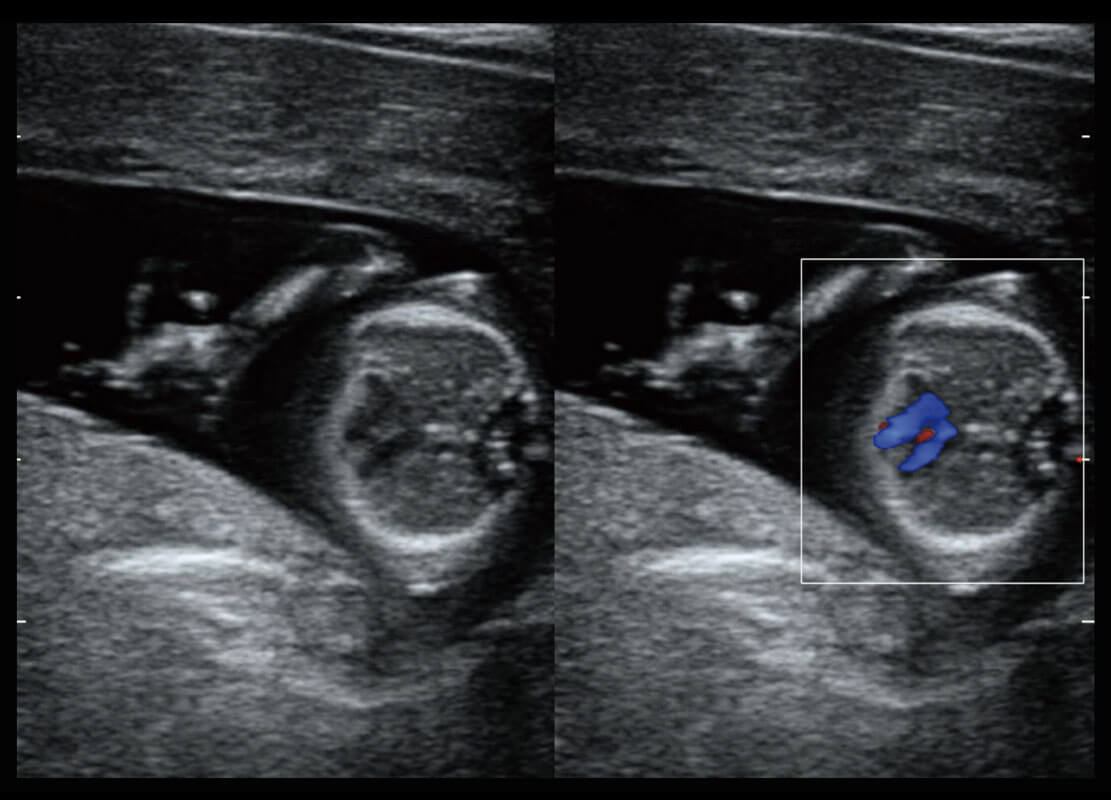

腔内三维-宫内节育器

P60搭载宽频带线阵探头、宽景成像、弹性成像技术,为您提供乳腺应用方案。P60支持高频相控阵探头、线阵探头、腹部高频探头、腹部微凸探头等,丰富的探头群搭载敏感的彩色血流成像,适用于新生儿多种脏器检测要求,满足新生儿筛查需求。

乳腺癌显微血流